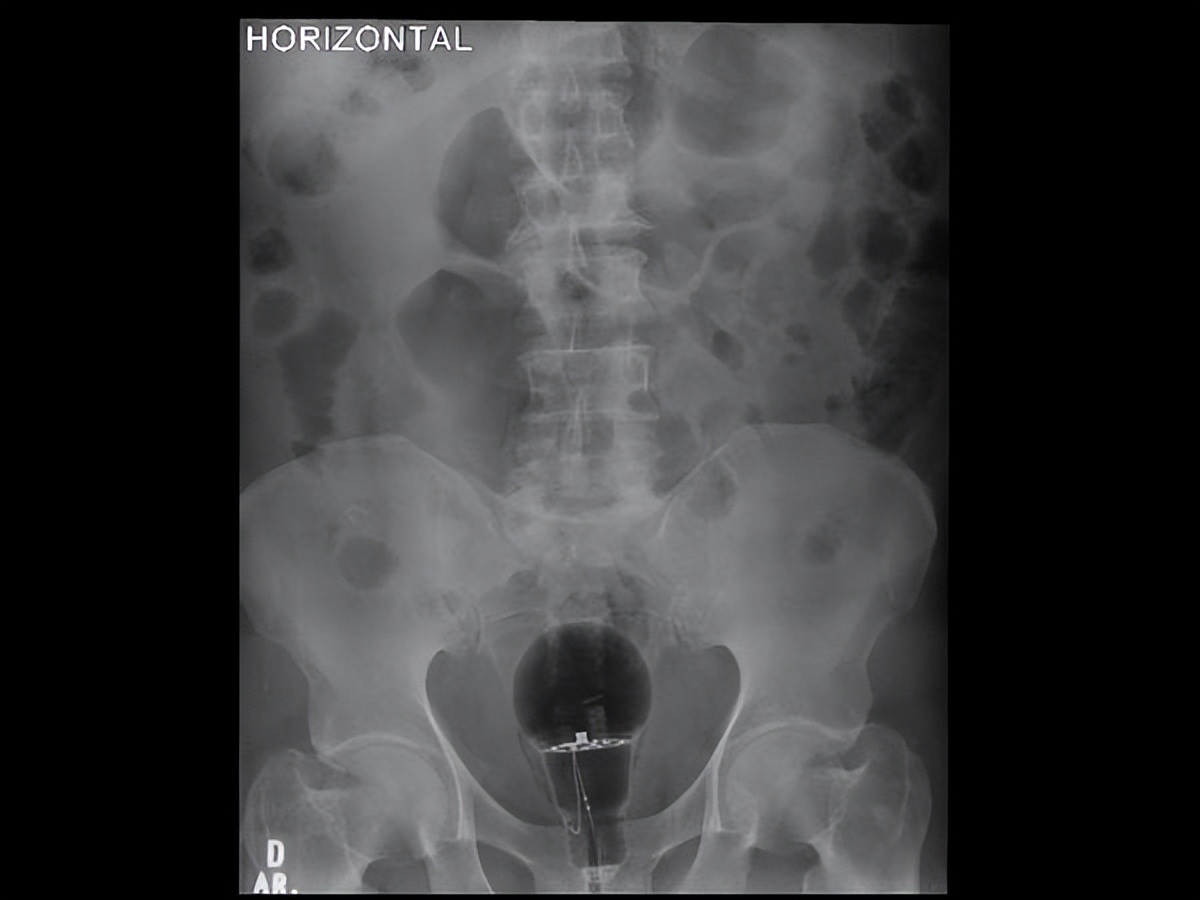

在接触到如此奇葩之事后,朱利安迫不及待地在推特上写道:“53岁男性患者,直肠指诊难以触及的体内(未知)异物,该用内视镜移除?”,并贴出一张X光照。

咱们从附图中可以看到,该病患骨盆位置附近出现一个大灯泡,甚至可以看到疑似金属电线的构造。

朱利安医生贴出的X光照